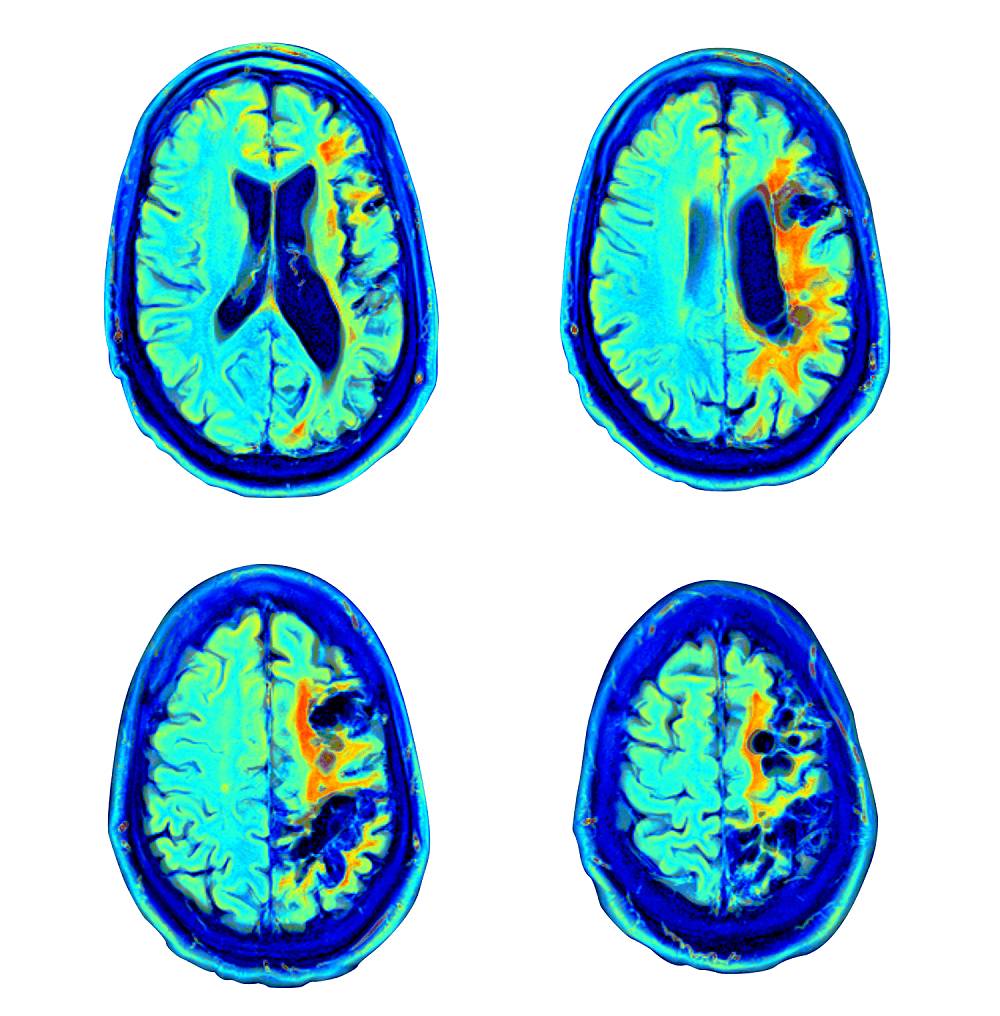

تحدث السكتة الدماغية عندما ينقطع تدفق الدم عن جزء من الدماغ بسبب انسداد أو تمزق الأوعية الدموية. ويمنع ذلك الدماغ من الحصول على الأكسجين الذي يحتاجه، وتبدأ الخلايا في الموت، مما قد يؤدي إلى إصابة الدماغ.

- زيادة تدفق الدم في أجزاء الدماغ المرتبطة بالإحساس والذاكرة والرؤية والانتباه، مما يؤدي إلى تحسين وظيفة الذاكرة، ومدى الانتباه، والوظيفة التنفيذية، وتعزيز القدرة على إدراك المعلومات بشكل أسرع.

- زيادة كبيرة في تدفق الدم إلى الدماغ (نضح الدماغ) وتوليد أوعية دموية جديدة في الدماغ (تكوين الأوعية الدموية).

- يعمل العلاج بالأكسجين عالي الضغط (HBOT) على تحفيز المرونة العصبية - قدرة الدماغ على التكيف/ الاستجابة للإصابة أو المرض - في الأجزاء المصابة من الدماغ، حتى بعد سنوات من الإصابة بالسكتة الدماغية.

تقييم طبي وفسيولوجي وذهني شامل على مدار ثلاثة أيام يقوم به طاقم Aviv الطبي المعتمد، والذي يضم نخبة من الأطباء، وخبراء علم النفس العصبي، والمعالجين الفيزيائيين، وأخصائيي علم وظائف الأعضاء، وفريق التمريض. ويشمل ذلك أكثر اختبارات تصوير الدماغ تطوراً بما يتناسب مع احتياجاتك – مثل التصوير بالرنين المغناطيسي لتروية الدماغ MRI، والتصوير بالرنين المغناطيسي الوظيفي fMRI، والتصوير المقطعي المحوسب بفوتون واحد SPECT.